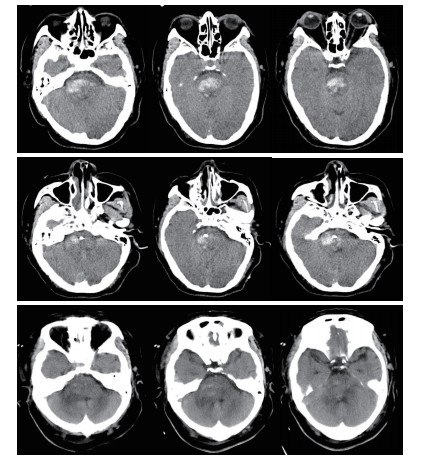

穿刺路径选择:行脑干出血立体定向穿刺分别采用幕上经额部及幕下经桥臂两种入路,笔者根据血肿的位置及患者的病情选择相应的入路,经幕上穿刺尤其适合侵及中脑的血肿,优点:体位摆放方便,对患者呼吸功能影响小,操作较简便,手术时间较短,血压监测较方便。缺点:穿刺路径较长,可能穿过脑室造成引流管移位,穿过丘脑及中脑,损伤损伤丘脑及中脑结构,如引流管置入过深可能损伤延髓。经幕下穿刺优点:经桥臂穿刺,穿刺路径短,损伤重要结构少,缺点:手术中需要侧卧位,可能影响呼吸,手术前应行气管插管,上头架时应预留手术穿刺位置,及耳环的位置,体位摆放及术中操作较复杂,手术时间较长。对于血肿侵及中脑或病情较重的患者,一般选择幕上经额穿刺(图 1)。如患者病情允许或术前有脑积水的患者,一般选择经幕下经桥臂入路,并根据血肿形态使引流管纵行穿过血肿(图 2)。

| 图 1 经幕上入路脑干血肿穿刺A:血肿穿刺前B:血肿穿刺后复查C:穿刺后5 d |

本组手术术后24 h内血肿大部排空有7例,24~48 h大部排空有11例,48~72 h大部排空8例(图 1,2)。于1~4 d内拔除血肿腔引流管。术后8例患者3个月内死亡,死亡率25.8%。1例术中突发血压持续降低后,术后弥漫性脑肿胀死亡。1例术前吸入性肺炎严重,术后感染性休克死亡。1例肝功能不全,术中术后反复出血,家属放弃治疗死亡。1例术后不明原因高热,消化道出血,家属放弃治疗死亡。2例术后突发呼吸心搏骤停死亡。2例术后再出血,家属放弃治疗死亡。18例于术后3个月内清醒,均留有不同程度残疾,5例3个月内未清醒,存活病例随访3个月至1年后,格拉斯哥结局量表(GOS) 5级5例,4级7例,3级6例,2级5例,1级8例。植物状态及死亡患者多为出血量大(>10 mL),术前昏迷程度较深的患者(GCS评分3~5分)。